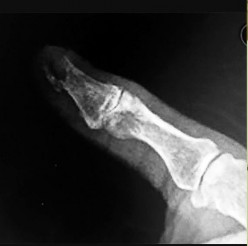

- الأشعة السينية (X-rays): هي الخطوة الأولى في تقييم الكسور، الخلوع، وتغيرات التهاب المفاصل. تساعد في تحديد مدى تدهور العظام والمسافات المفصلية. على سبيل المثال، تُظهر صور الأشعة السينية كسور السلاميات

أو كسور قاعدة العظم المشطي الخامس